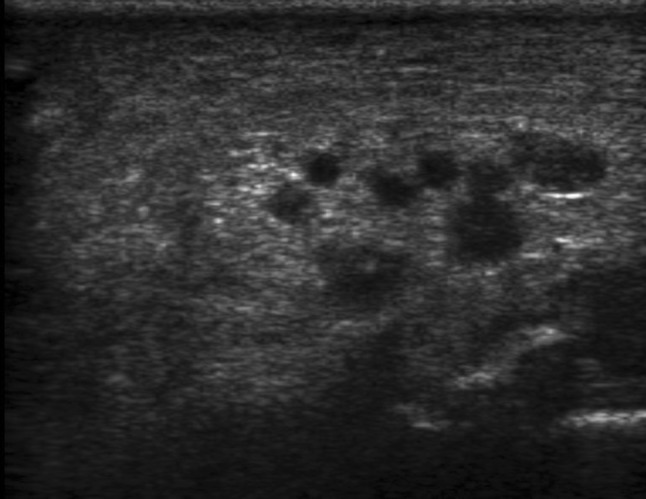

Herein, we report the case of a 16-year-old female who presented to the orthopaedics clinic with the complaint of a painless soft tissue swelling involving the right ankle and foot. She first noted the swelling at about 8 years of age. Initially, it was small, but later, the lesion gradually painlessly progressed to the present size. It completely surrounded the ankle and the heel region. The involved region experienced overgrowth compared to that on the opposite side. The skin over the swelling was normal with no evidence of any discolouration. On palpation, the temperature of the lesion was not raised. The lesion was soft to touch, but it was not possible to distinguish the margins from the adjacent normal area, suggesting an ill-defined lesion. In consistency with the examination findings, the provisional diagnosis of a vascular malformation was considered. The patient was subjected to ultrasonography. It showed an increase in the thickness of the soft tissue, which appeared hyperechoic, comparable to the adjacent normal fat density with multiple interspersed hypoechoic areas within it (Fig. 1). On colour Doppler evaluation, these hypoechoic areas showed slow flow, which it was better to appreciate on power Doppler (Fig. 2). These findings were consistent with the diagnosis of a vascular malformation. However, the duration of the progression of the supposed vascular malformation and the absence of phleboliths on the ultrasound and the subsequent X-ray raised suspicion regarding the diagnosis of a vascular malformation. A second differential of a neurofibroma was considered. Subsequently, a biopsy was conducted. It showed elongated spindle cells with poorly defined, pale eosinophilic cytoplasm and tapering, wavy, or buckled nuclei admixed with a few small nerve fibres (Fig. 3). Immunohistochemistry showed positivity for S-100 (Fig. 4). These findings were consistent with the diagnosis of diffuse neurofibroma.

Fig. 1.

Shows an ill-defined hyperechoic lesion around the ankle and the heel with multiple interspersed hypoechoic areas within it

On ultrasonography, the superficial subcutaneous lesions appear to be hyperechoic masses fenestrated by hypoechoic foci that represent the blood vessels [1, 4]. Similar findings were noted in the present case. However, few reported cases show deeper involvement of the structures, presenting as hypoechoic masses infiltrating the adjacent structures [4]. Ultrasound has been agreed upon as the initial modality of investigation due to its easy availability, lack of radiation exposure, and cost-effectiveness [1, 3, 4]. However, more deeply infiltrating lesions may require an MRI to delineate their exact extents. On MRI, most of these lesions are depicted as isointense or mildly hyperintense compared to muscle on T1-weighted images and mildly or markedly hyperintense compared to muscle on T2-weighted images. Such findings have been consistently described in various case reports [4, 8].